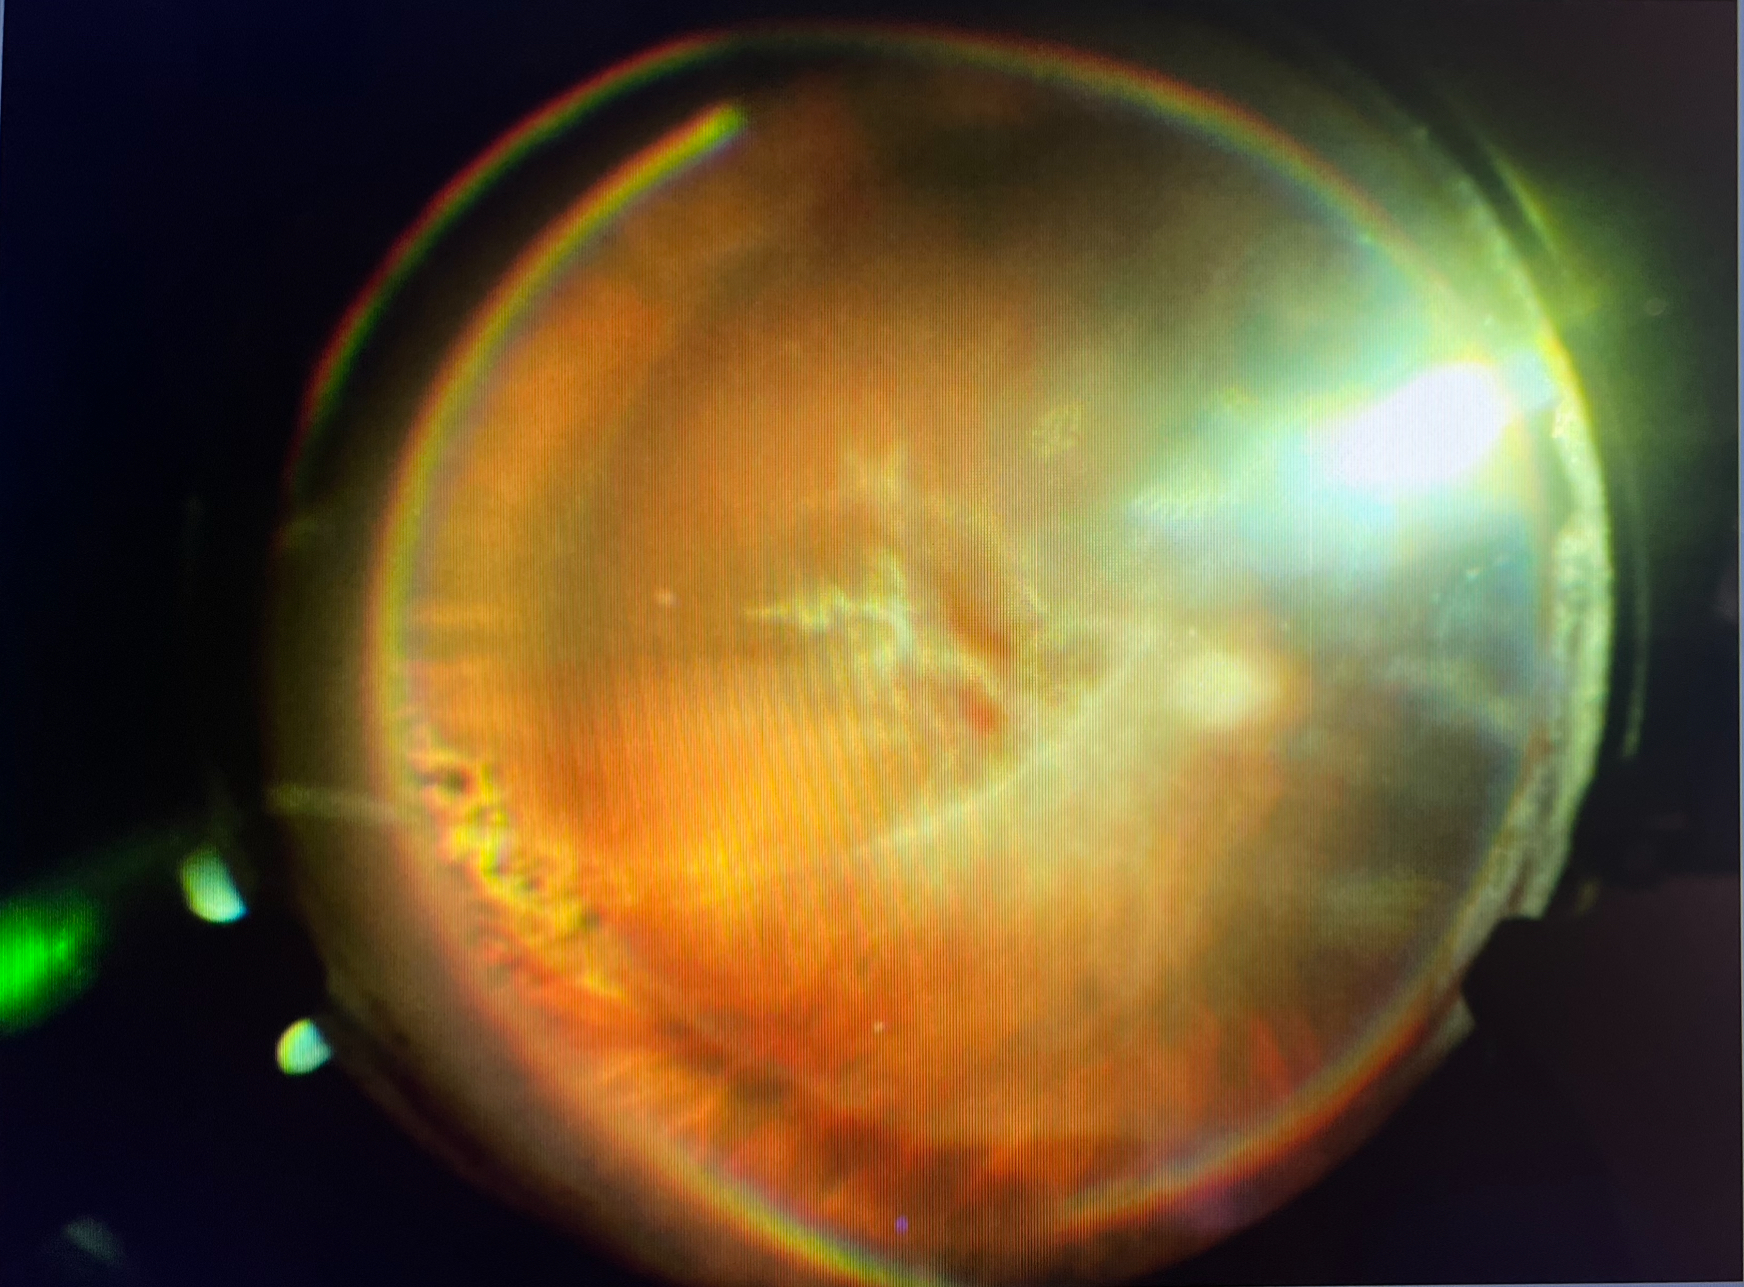

今日の硝子体手術の73歳の男性の方は、当院の職員のお父さまでした。元々、右眼の硝子体出血があったのですが、白内障もそれなりに進行していたので、11月にまずは白内障の手術を受けていただきました。しかし、白内障を取ってみると、硝子体出血の量も多く、視力もわずかに改善したのみでした。幸い、その後の左眼の白内障の手術の後は、視力も十分改善し、それほど不自由もなかったため、患者さまの希望も踏まえ、しばらく保存的に経過を見る方針とさせていただきました。ただ、出血の原因がはっきりしなかったので、あまりそのままにしておくのもよくないのと、やはりなかなかこのままでは出血が引きそうになかったので、今回、出血を取る硝子体手術をさせていただきました。出血を取ると、白くなった血管(白線化血管)とその周りにレーザーの跡があり、網膜静脈閉塞症が原因の出血と思われ、網膜剥離や加齢黄斑変性などの悪い原因での出血ではなく、このまま出血がひいてくれれば、視力も期待できそうだったので、よかったです。ただ、白線化血管の上に膜が形成され、それを取り除こうとしたら、膜の中にできた血管から出血が起こり、熱凝固して止めましたが、術後にジワジワ出血することがあるので、注意して経過をみていきたいと思います。